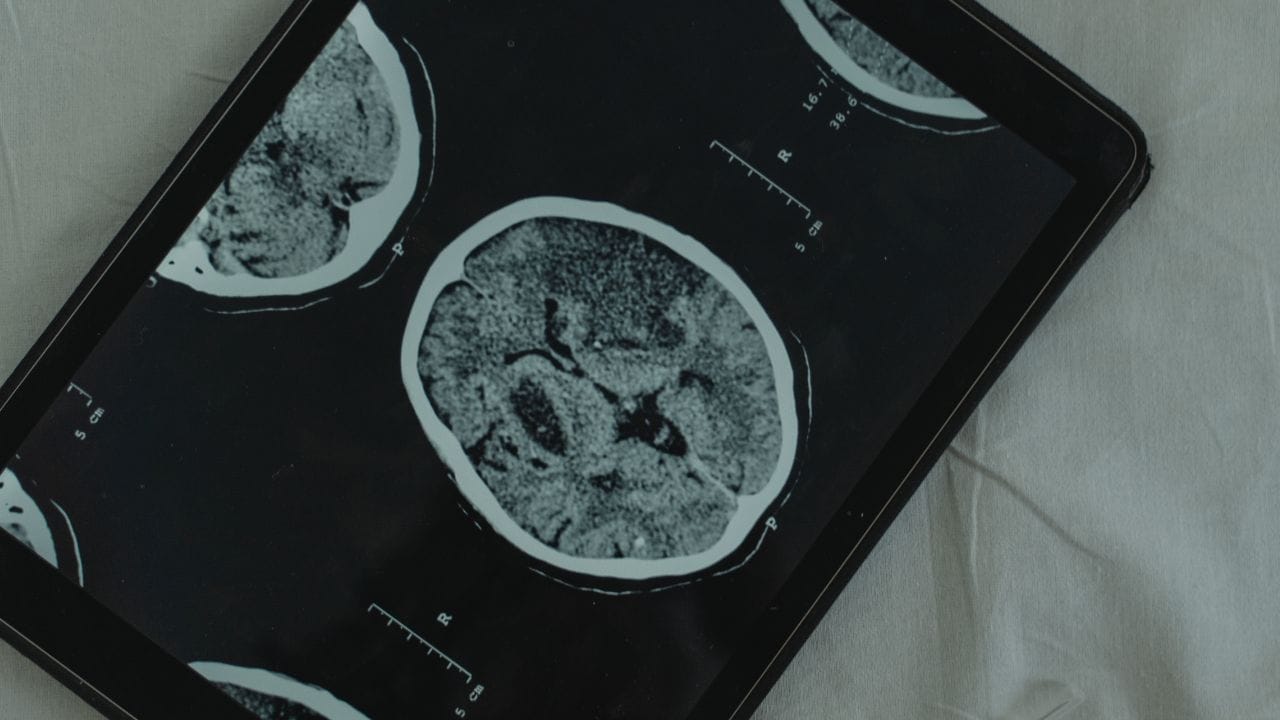

Diagnóstico: exames essenciais

O diagnóstico de um glioma combina avaliação clínica, exames de imagem e testes laboratoriais para confirmar o tipo e orientar o tratamento.

- Exames de imagem: a ressonância magnética é o método mais indicado para identificar e caracterizar o tumor; a tomografia pode ser usada em situações emergenciais ou como exame complementar.